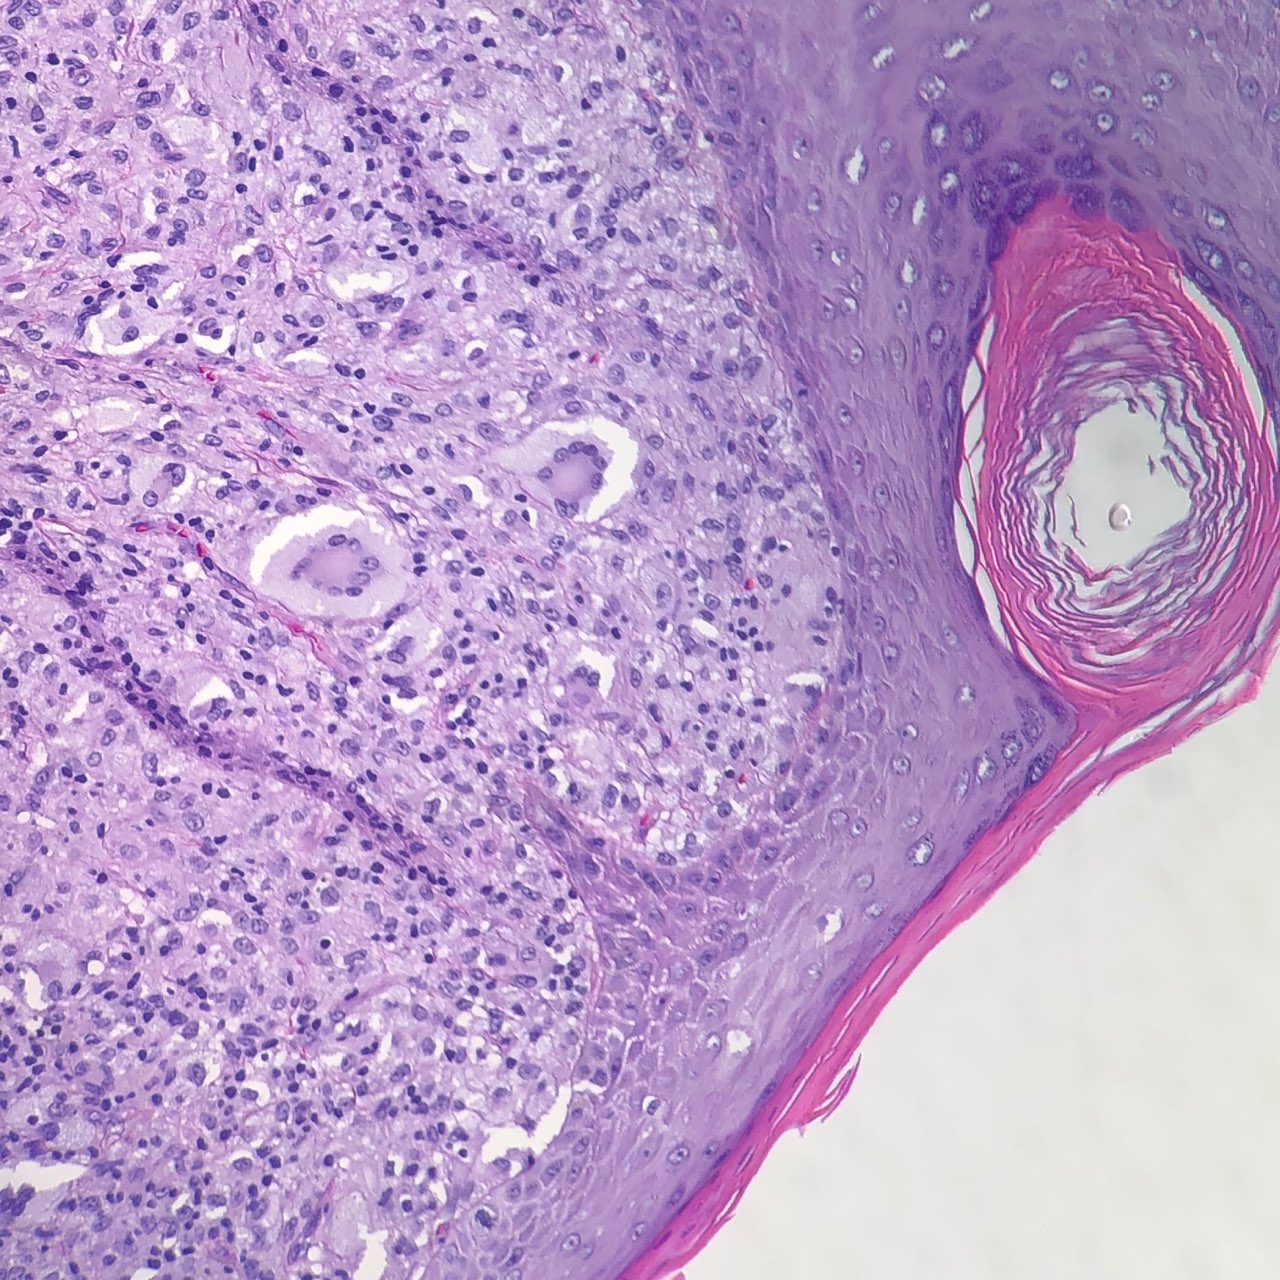

Verruciform Xanthoma - Mayo Clinic Proceedings

image size: 2242x1599